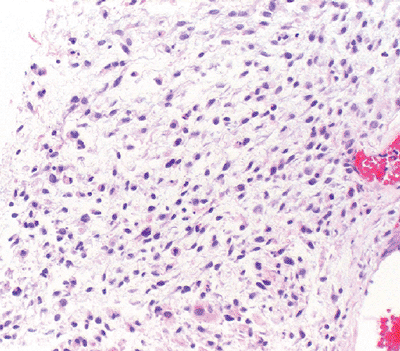

Histology: mature adipocytic tissue with slight atypia and scattered to rare lipoblasts (Fig. 12-1)

![]() |

|

Figure 12-1

Well differentiated liposarcoma; relatively mature adipocytic tissue with varying cell size admixed with hyperchromatic and multinucleated stromal cells. |